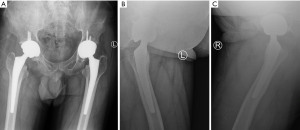

Although medication was administered, there was no significant relief in hip pain symptoms. The X-ray examination of the patient showed severe collapse of both femoral heads, narrowing of the hip joint space, and subluxation of the left femoral head in our hospital (Figure 2). Computed tomography (CT) examination showed that the patient’s bilateral femoral head joint surfaces were fractured, and multiple cystic changes and necrosis occurred within the femoral head (Figure 2). Hip joint magnetic resonance imaging (MRI) examination showed mixed signals in the femoral head, as well as typical “double line sign” and “map sign” manifestations (Figure 2). The patient was diagnosed with bilateral ANFH [Association Research Circulation Osseous classification stage IV (ARCO IV)] according to the diagnostic criteria of the ARCO (6).

The preoperative laboratory test results of the patient showed severe deficiencies in red blood cells, granulocytes, and platelets, elevated venous blood glucose, and no significant abnormalities in chest CT, lung function, and ultrasound examinations of abdominal, cardiac, and lower limbs vascular. We administered multiple component infusions of red blood cells and platelets before surgery. To increase the number of platelets, we orally took 75 mg of eltrombopag tablets daily. We subcutaneously injected recombinant human granulocyte colony-stimulating factor (300 µg) the following day to increase granulocyte levels. We maintained the intravenous glucose of this patient through continuous insulin administration and a strict diabetic diet. We maintained the patient’s blood levels, blood sugar, biochemistry, and coagulation function at a reasonable level during the perioperative period. We performed THA on the patient’s hip joint through the posterior lateral approach under general anesthesia in January 2024 and March 2024, and the two surgeries went successfully without any adverse events. We performed pelvic X-ray examination after surgery and found that the hip joint prosthesis was in good position (Figure 3). The patient had no obvious discomfort symptoms after getting out of bed and moving around. We followed up for 6 months and both hip functions recovered well (Harris Hip Score =90 points).